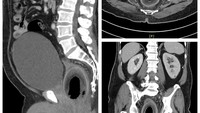

Dokter menemukan sebuah kelapa di dalam rektum seorang pria di Taiwan. Setelah di rontgen, kelapa itu berukuran panjang sekitar 7,5 cm dan lebar 5,7 cm. (Foto: British Journal of Surgery)